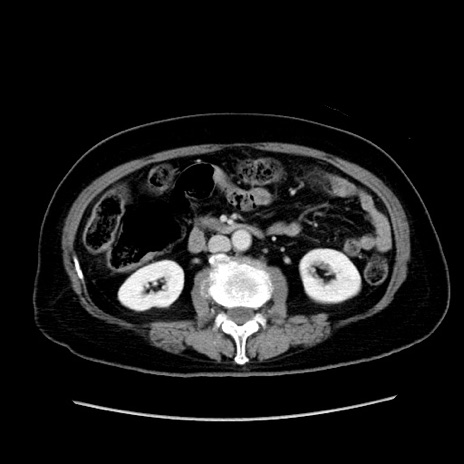

症例19(横断像)

【症例】80歳代女性

【主訴】下腹部痛

【現病歴】約8時間前より下腹部痛の出現あり、救急外来受診。

【既往歴】両側付属器切除

【身体所見】意識清明、下腹部正中に手術痕あり、その部位に一致して圧痛と反跳痛あり。腸蠕動音は亢進。

【データ】WBC 9300、CRP 0.15